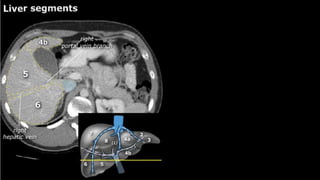

•Liver • A normalliver enhances homogeneously (irrespective of the scan phase). The liver receives about 80% of its blood through the portal vein (= nutrient-rich blood from the intestines). The remaining 20% is supplied by the hepatic artery. y is present, it is important to document its location. This may be crucial to any surgical options. Using the Couinaud classification, the liver is subdivided into eight individually functioning segments. Each segment has its own afferent hepatic artery and portal vein, and efferent hepatic vein and efferent bile ducts

y is present, it is important to document its

location. This may be crucial to any surgical options. Using the

Couinaud classification, the liver is subdivided into eight individually

functioning segments. Each segment has its own afferent hepatic

artery and portal vein, and efferent hepatic vein and efferent bile

ducts